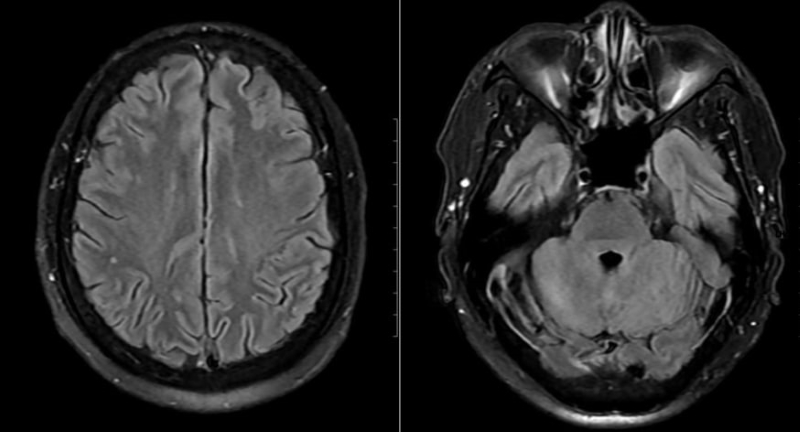

Mặc dù chưa có biểu hiện thần kinh rõ ràng, bệnh nhân vẫn được chọc dò dịch não tủy để loại trừ biến chứng. Kết quả cho thấy dịch não tủy có tăng tế bào và protein, phản ứng Pandy dương tính, xác định viêm não - màng não. Bên cạnh đó, hình ảnh MRI sọ não phát hiện ổ tổn thương nhỏ tại thùy chẩm trái.

Tổn thương phát hiện trên phim chụp MRI của bệnh nhân

Từ các dữ liệu lâm sàng và cận lâm sàng, bệnh nhân được chẩn đoán mắc nhiễm khuẩn huyết - viêm não màng não do Streptococcus suis.

Ngay khi nhập viện, bệnh nhân được điều trị kháng sinh đường tĩnh mạch và hiệu chỉnh khi có kết quả kháng sinh đồ, kết hợp theo dõi sát tình trạng toàn thân và thần kinh. Sau 24 giờ, bệnh nhân cắt sốt, thể trạng cải thiện rõ rệt. Sau 15 ngày điều trị tích cực, các xét nghiệm và hình ảnh học cho thấy tổn thương đã hồi phục hoàn toàn, bệnh nhân xuất viện trong tình trạng ổn định, không để lại di chứng thần kinh.